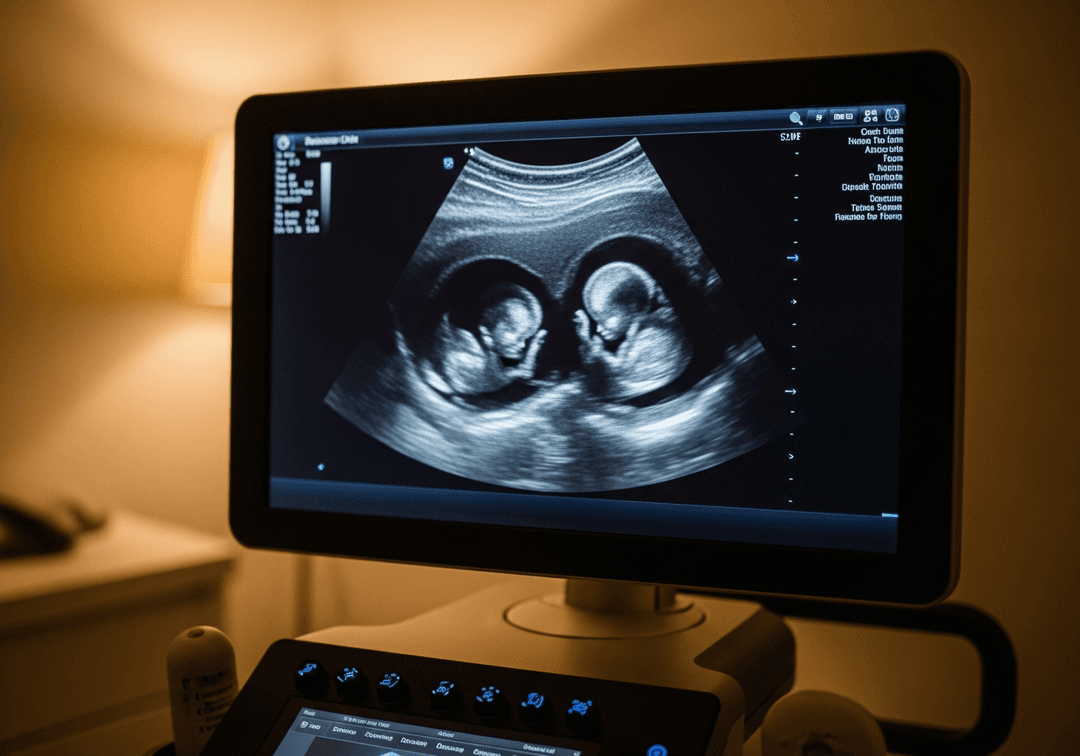

Les différents types de grossesses gémellaires

La détermination du type de grossesse gémellaire est essentielle dès le premier trimestre car elle conditionne la surveillance. L'échographiste recherche le nombre de placentas et de poches amniotiques.

- Monochoriale biamniotique : 1 placenta, 2 poches (jumeaux identiques)